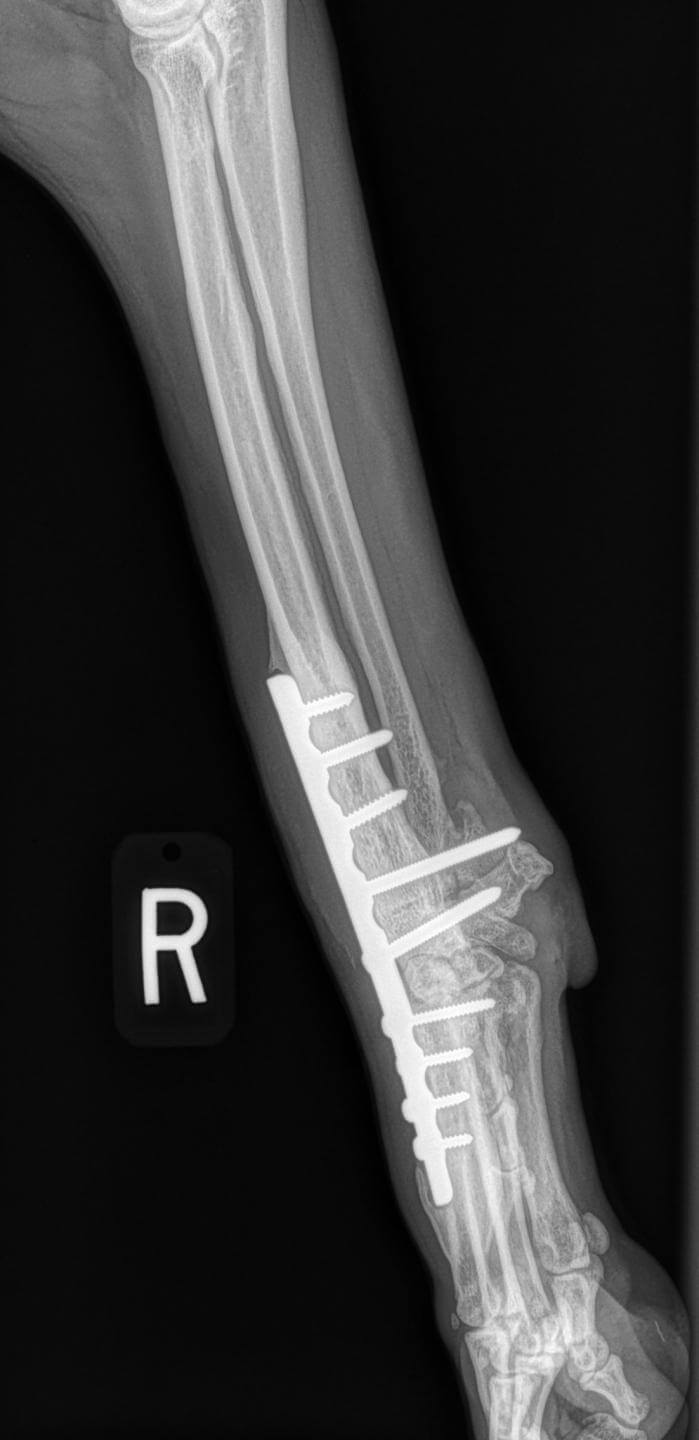

Severe, high-grade sprain injuries and most forms of degenerative hyperextension are usually treated by fusion of the carpal joint. This procedure is called pancarpal arthrodesis. Pancarpal arthrodesis involves the fusion of the forelimb (antebrachium) with the paw across the carpal joint using a combination of plates and screws. We have led the field in the development of new technologies of internal and external skeletal fixation in this arena.